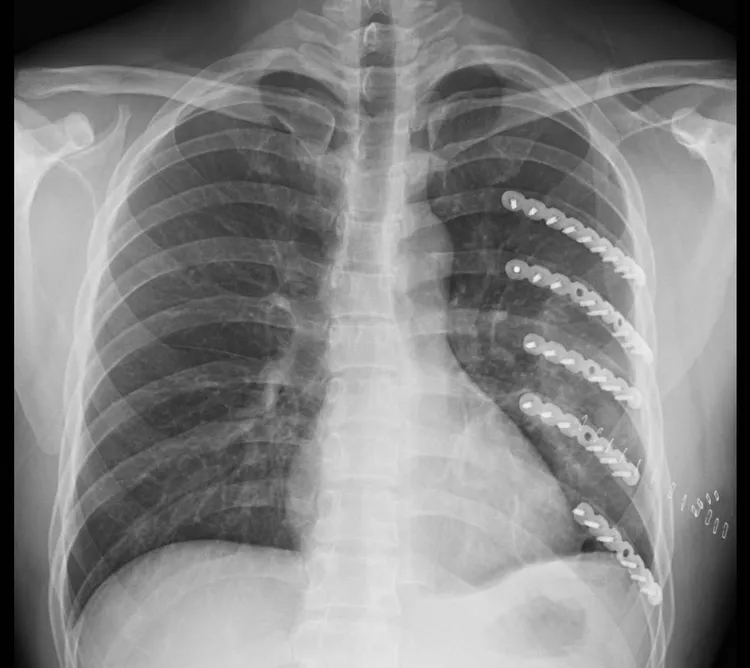

林聿騰指出,為減少病患的身體負擔,採用最新設備,配合3D胸廓重組影像精準定位,用最小傷口的微創手術進行復位,再以肋骨專用的鈦合金板固定,將傷口縮小到只有9公分,術後狀況良好。